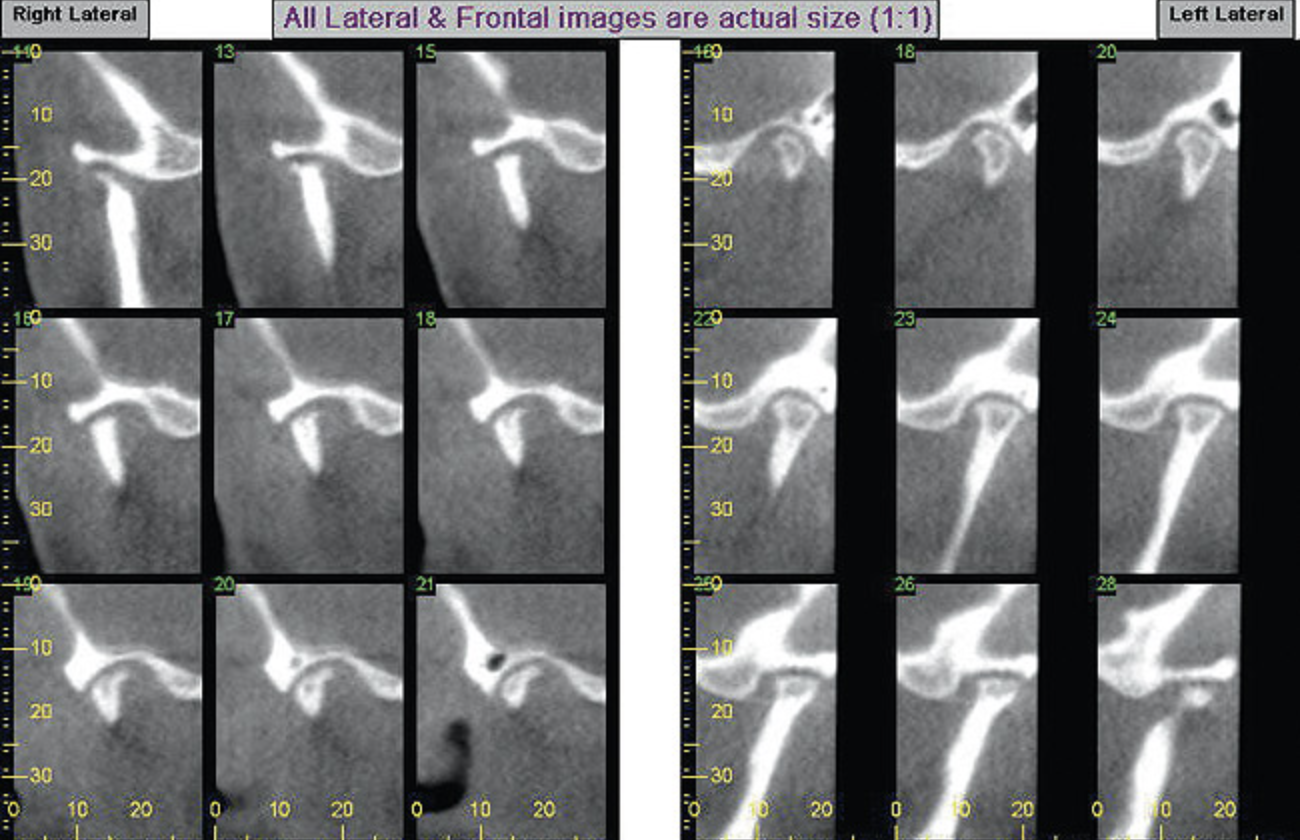

A stable TMJ is critical in establishing a normal functional occlusion. Unless the condyles are in a stable musculoskeletal position, there are always interferences to normal function and stress placed on the masticatory system.1-3,15 In orthodontics, the Angle classification of malocclusion using handheld models has been the standard to evaluate the fit of the teeth. However, it is not possible to truly identify the occlusion/malocclusion using handheld models. Before the occlusion can be evaluated, the clinician must ascertain the joint position and condition (Figure 7 and Figure 8).1,16

Figure 7A  This case is an example of the importance of evaluating the bite with the joints seated in a stable position. Orthodontic treatment was rendered to correct a "deep overbite" and trauma to the maxillary incisors. A) Handheld models in maximum intercuspation at beginning of treatment. The deep overbite is apparent.

Figure 7A

Figure 7B  This case is an example of the importance of evaluating the bite with the joints seated in a stable position. Orthodontic treatment was rendered to correct a "deep overbite" and trauma to the maxillary incisors. B) Handheld models showing correction of the deep overbite after orthodontics has been completed. The patient complained of "jaw" discomfort after orthodontic treatment.

Figure 7B

Figure 7C This case is an example of the importance of evaluating the bite with the joints seated in a stable position. Orthodontic treatment was rendered to correct a "deep overbite" and trauma to the maxillary incisors. C) Models mounted in CR after use of a superior repositioning splint to stabilize the joints. With stabilized joints, the true malocclusion is uncovered. The patient went back into orthodontic treatment and required mandibular advancement surgery.

Figure 7C

Figure 7D  This case is an example of the importance of evaluating the bite with the joints seated in a stable position. Orthodontic treatment was rendered to correct a "deep overbite" and trauma to the maxillary incisors. D) Models mounted in CR after retreatment.

Figure 7D